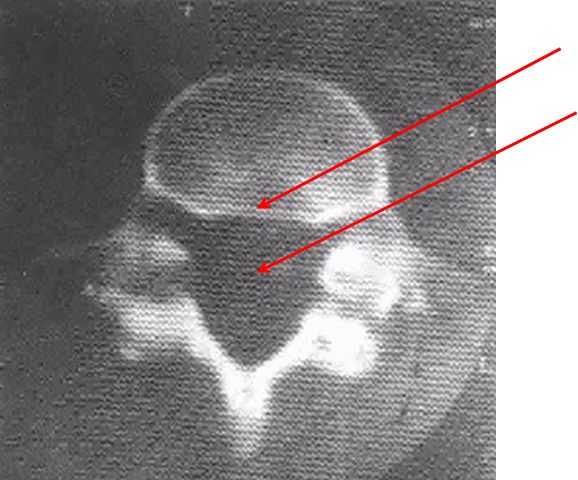

椎体滑脱程度分级- Meyerding分级,一般分为4级,也有5级分法,并不冲突。

将下位椎体上缘分为4等分,依据上位椎体对下位椎体向前滑移的程度分为4度。

Ⅰ度: 椎体向前滑移程度不超过椎体中部矢状径的1/4(0-25%);Ⅱ度: 椎体向前滑移程度超过椎体中部矢状径的1/4,但不超过2/4(25-50%);Ⅲ度: 椎体向前滑移程度超过椎体中部矢状径的2/4,但不超过3/4(50-75%);IV度: 椎体向前滑移程度超过椎体中矢状径的3/4(75%-100%);V度:椎体向前滑移程度>100%。

Ⅰ度

腰4椎弓峡部裂、腰4椎体向前 I 度滑脱

Ⅱ度

腰4椎弓峡部裂、腰4椎体向前 II度滑脱

Ⅲ度

腰4椎体向前 III度滑脱

IV度

V度